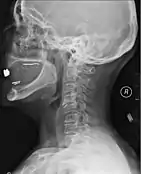

X-rays (left) are more available, but can miss details like herniated disks that MRIs can show (right).[85]

A radiographic evaluation using an X-ray, CT scan, or MRI can determine if there is damage to the spinal column and where it is located.[9] X-rays are commonly available[85] and can detect instability or misalignment of the spinal column, but do not give very detailed images and can miss injuries to the spinal cord or displacement of ligaments or disks that do not have accompanying spinal column damage.[9] Thus when X-ray findings are normal but SCI is still suspected due to pain or SCI symptoms, CT or MRI scans are used.[85] CT gives greater detail than X-rays, but exposes the patient to more radiation,[87] and it still does not give images of the spinal cord or ligaments; MRI shows body structures in the greatest detail.[9] Thus it is the standard for anyone who has neurological deficits found in SCI or is thought to have an unstable spinal column injury.[88]